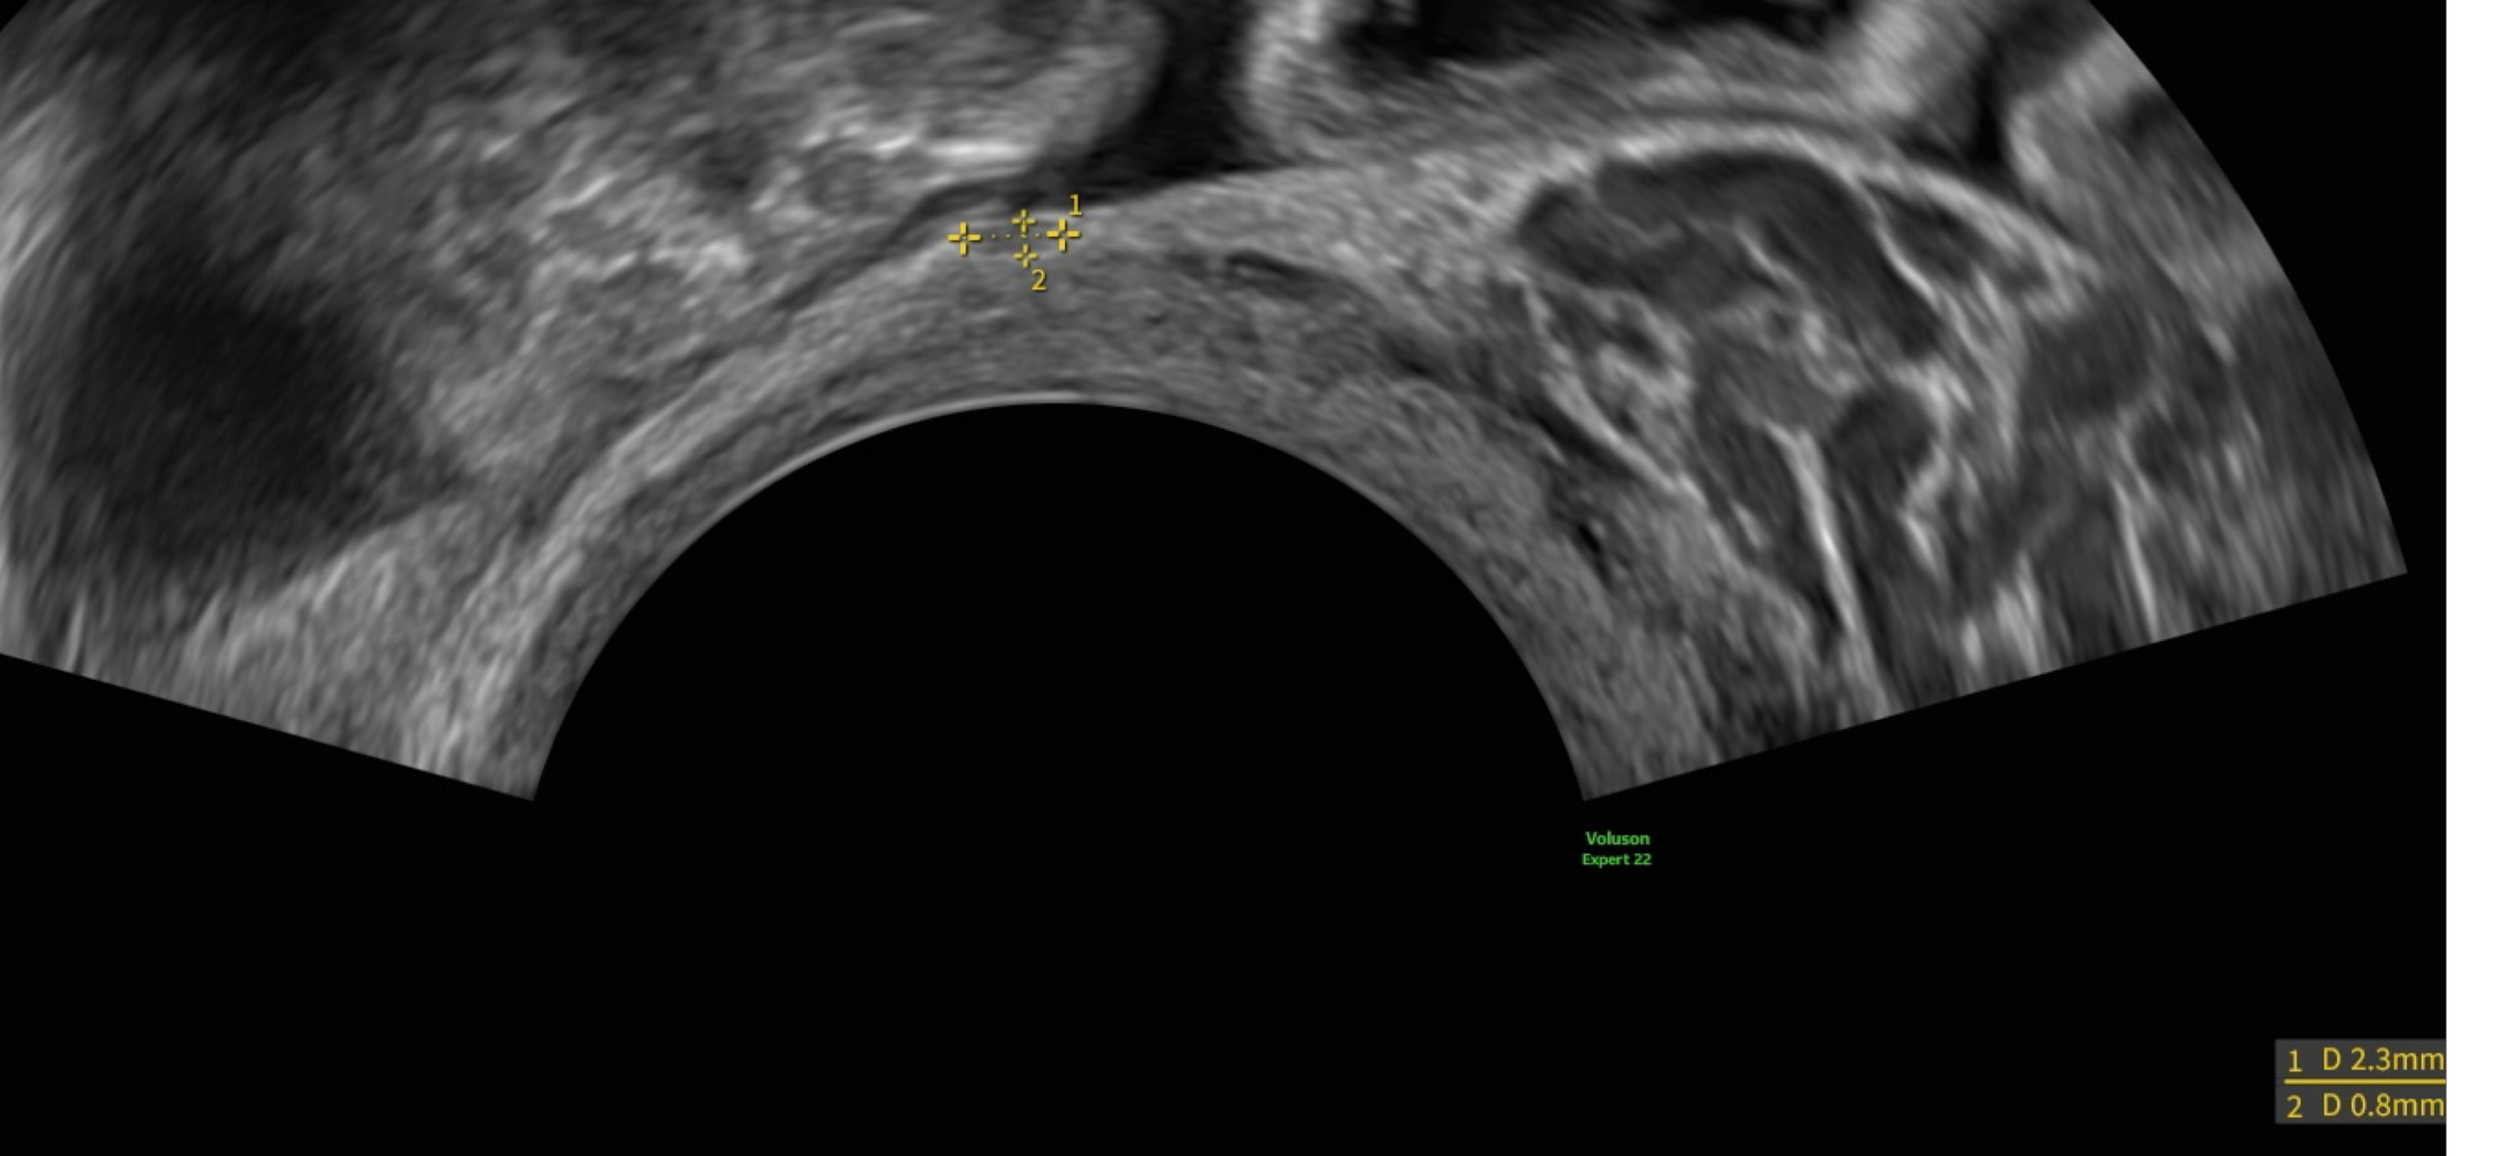

Obtaining a Diagnosis

Endoscan Health is led by Mr Tom Holland, Consultant Gynaecologist, specialising in endometriosis diagnosis and surgery.

We are focused on reducing the time to an accurate diagnosis.